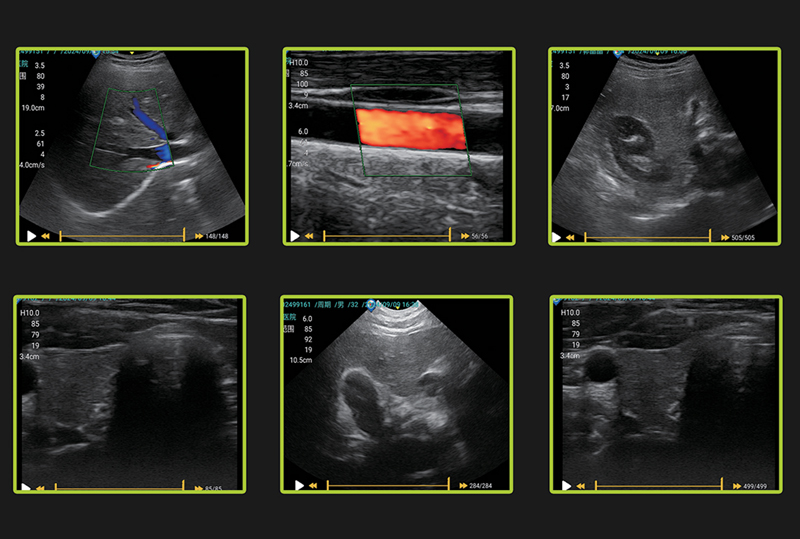

Laptop Color Doppler RK-C5N

- Rich imaging modes

- Advanced imaging technologies

Abdomen, Obstetrics, Gynecology, Small Organs

The RK-C5N is a color Doppler ultrasound diagnostic system with a laptop-style design. It integrates high-performance ultrasound imaging technology in a compact and lightweight body, balancing portability with clinical diagnostic needs, and is suitable for multiple departments and various application scenarios.

-Image mode: B,M,2B,B/M,4B,PW,PDI,Color

-Transducer frequency: Convex 2.5/3.5/4.0/5.0, linear 6.0/7.5/8.0/9.0/10/11, Micro-Convex 5.0/6.0/6.5/7.0/7.5/8.0,Transvaginal 5.0/6.5/7.0/7.5

-Cine-loop: 334 frame cine loop memory

Software packages: Abdomen, OB, gynecology, small Part